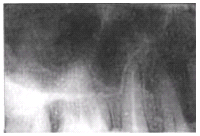

Здоровье зубов: периодонтальная щель и её значение